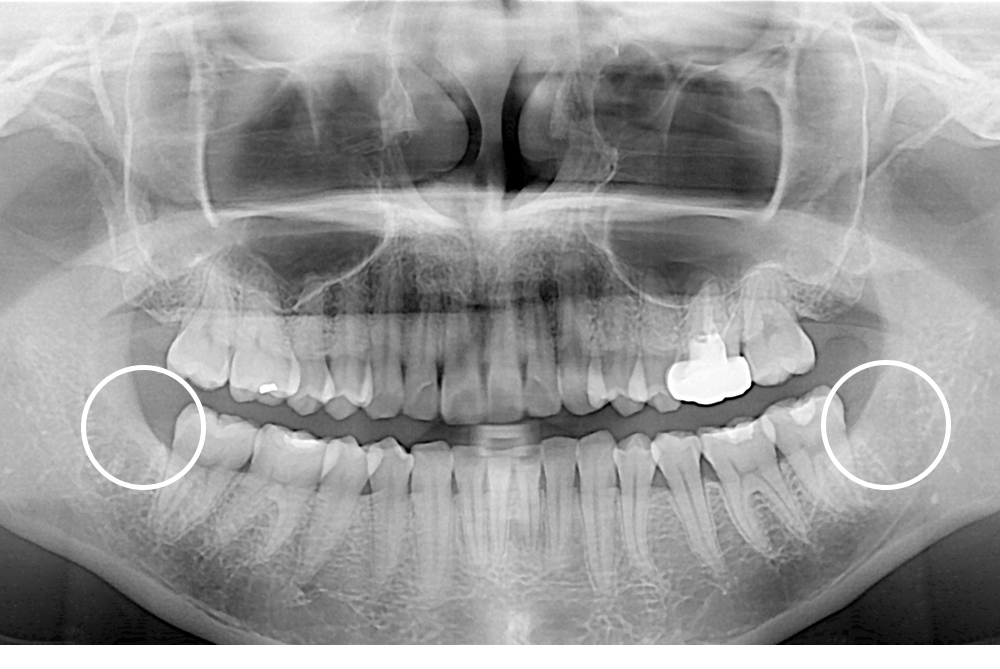

[사랑니] 매복 사랑니 발치

치료후 : 2016-01-28

세종치과는 구강악안면외과학 박사이신 원장님이 발치하는 치과입니다.